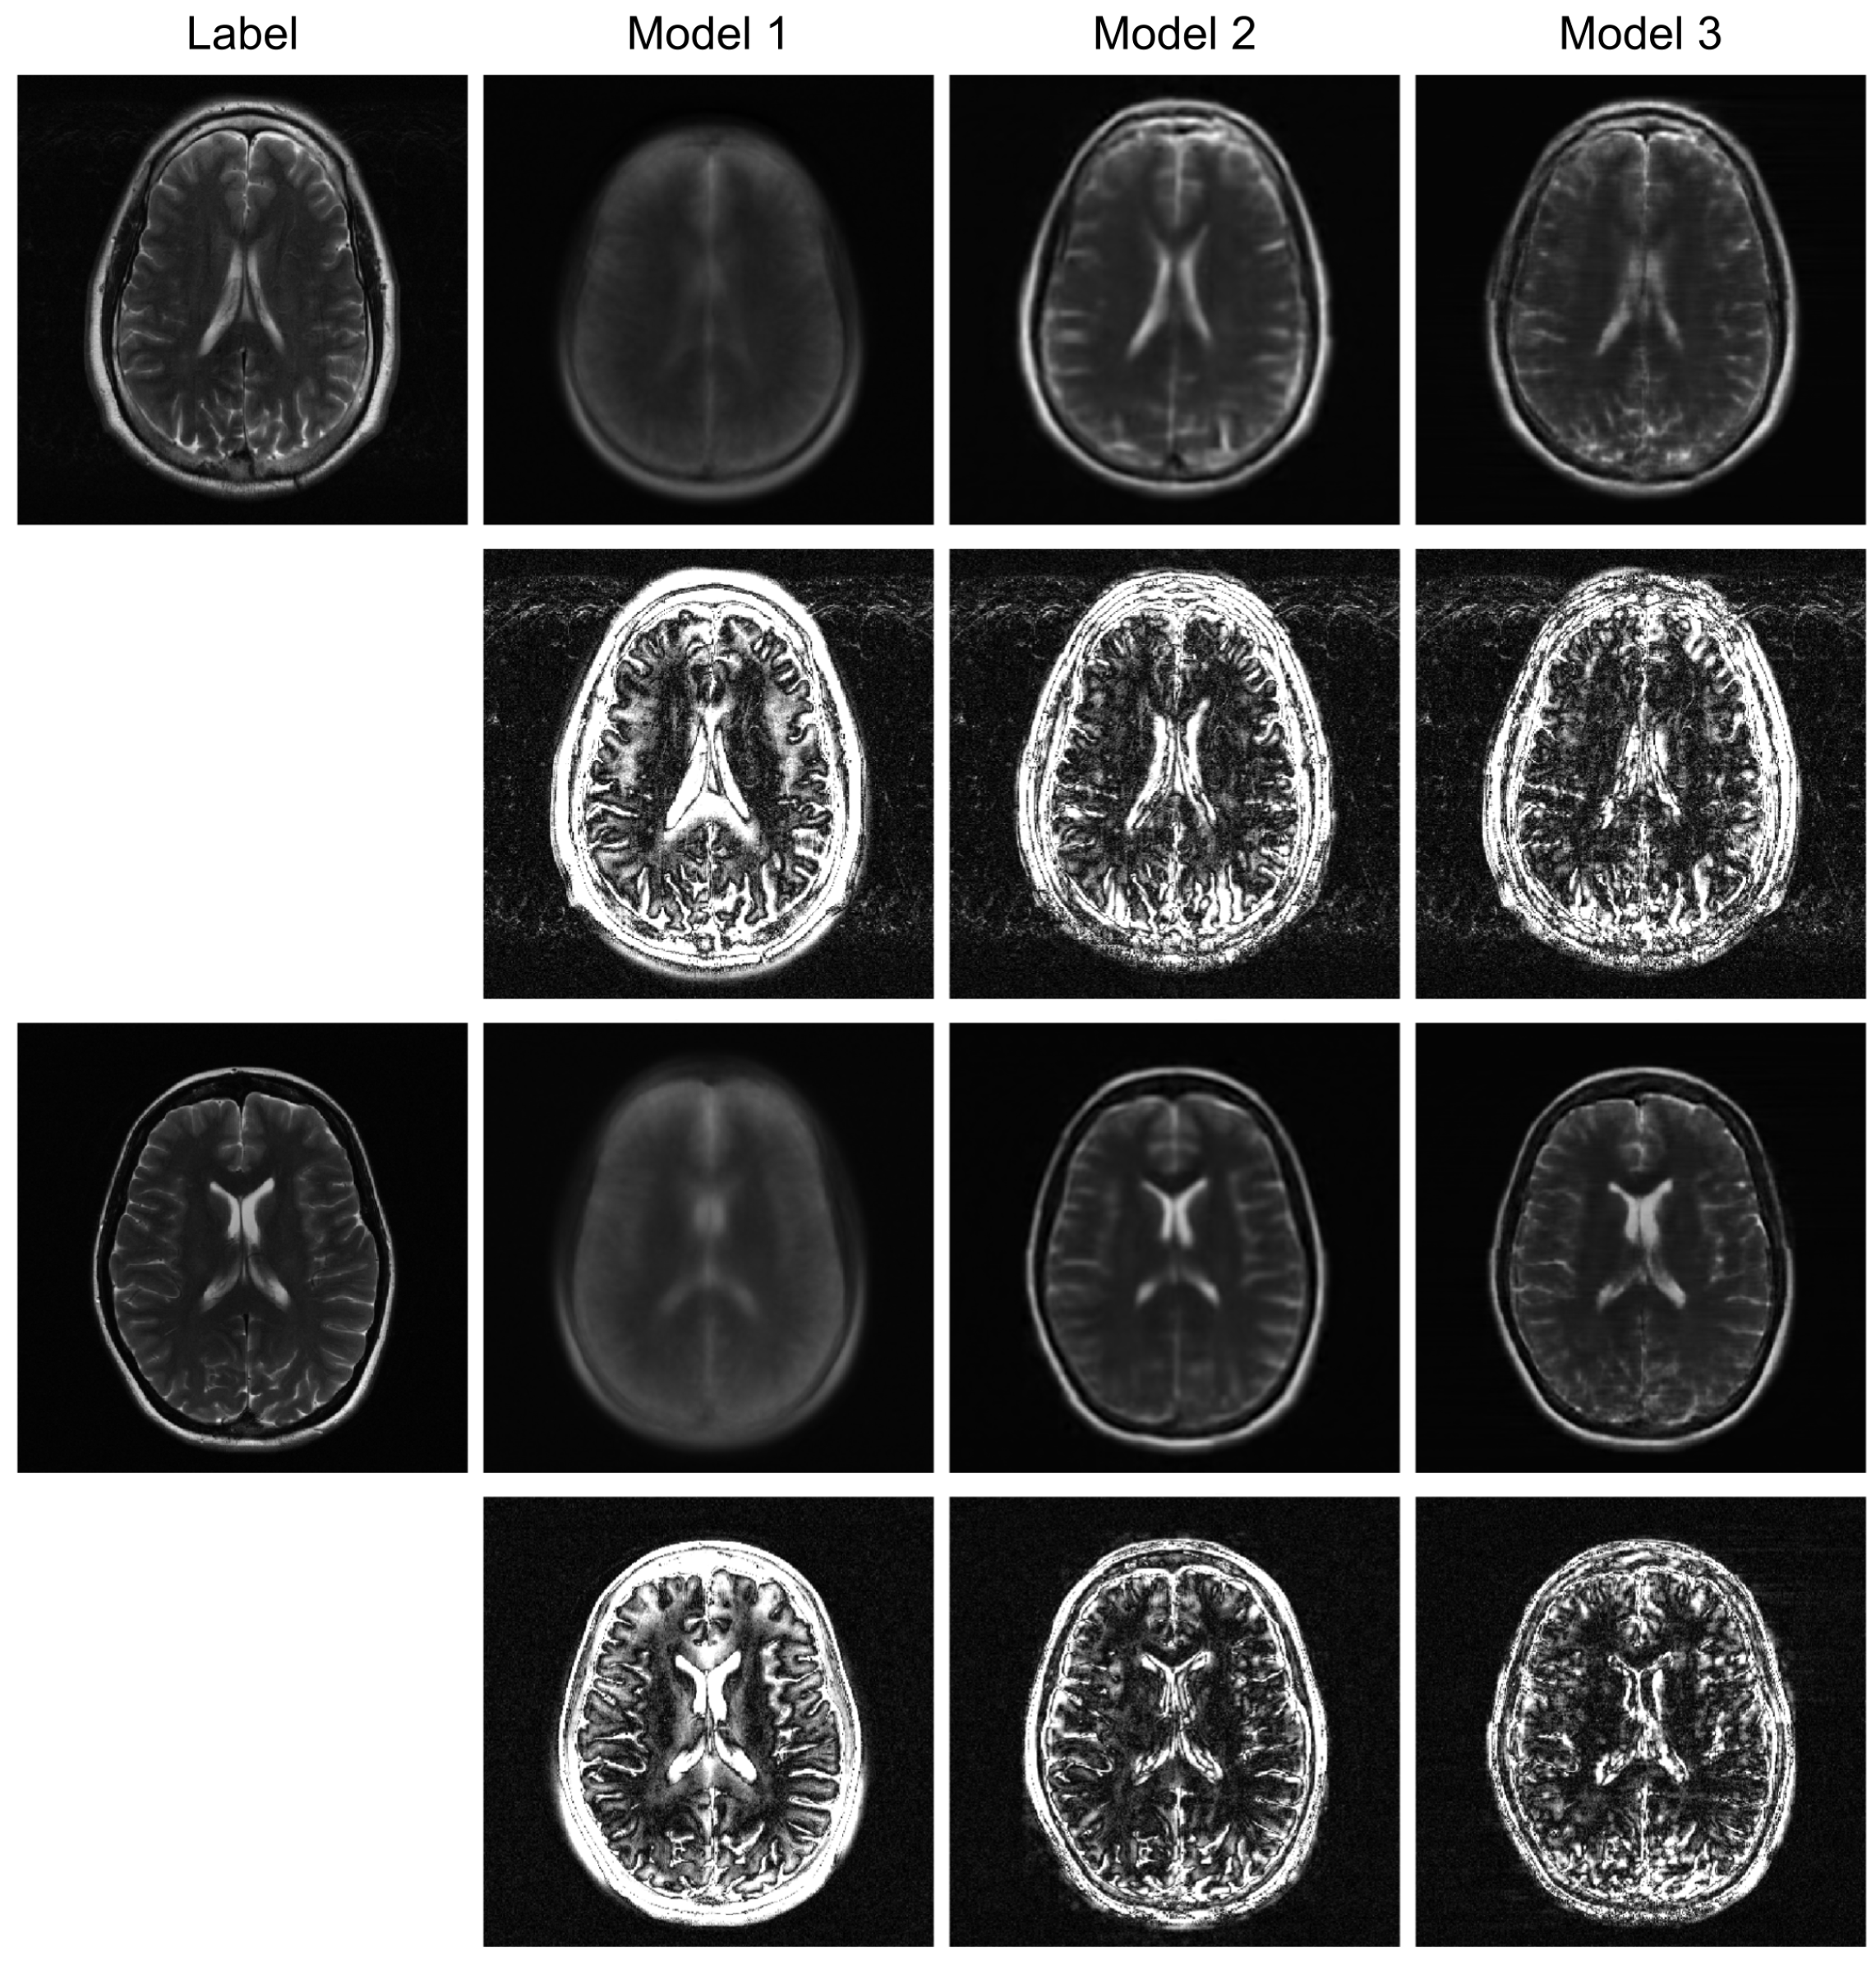

Figure 3 illustrates sample images and the corresponding error maps from Models 1–3, UNet, and VarNet for the R = 4 regular sampling pattern. The first column shows the reference (label) images, while columns 2–6 show the reconstructed images and the corresponding error maps (10× amplification) from UNet, VarNet, and Models 1, 2, and 3, respectively. Table 1 provides the quantitative results for the R = 4 regular sampling pattern.

A qualitative visual assessment of the reconstructed images in Figure 3 reveals significant performance differences among the models. The proposed Model 3 demonstrates exceptional reconstruction quality, achieving high fidelity to the reference image that is visually comparable to the performance of the UNet. Furthermore, the proposed model exhibits competitive performance against VarNet. As shown in Table 1, Model 3 achieves higher SSIM and VIF compared to VarNet, indicating superior perceptual quality and structural fidelity. The error map for Model 3 shows minimal structural error and low residual noise, indicating a successful recovery of fine anatomical details. In contrast, Model 1, which simply utilizes a final MLP for reconstruction, fails to capture essential anatomical structures, resulting in a severely blurred image with a high degree of structured error, as evidenced by its error map. Model 2, which employs a Transformer-based decoder, shows a substantial improvement over Model 1 by reconstructing the overall brain morphology. However, its error map contains more noticeable residual artifacts and noise compared to Model 3, suggesting a less complete removal of aliasing effects.

Figure 4. Qualitative evaluation on R = 4 randomly undersampled data. This figure compares the reconstruction outcomes and amplified (10×) error maps for Model 1, Model 2, and the proposed Model 3.